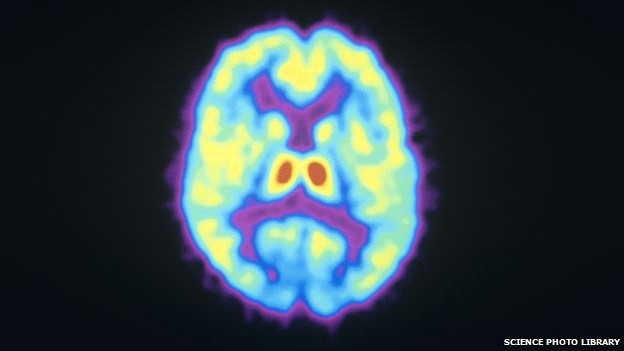

Hệ thống giảm đau của não hoặc hệ thống tưởng thưởng, phát màu đỏ và vàng khi được quét